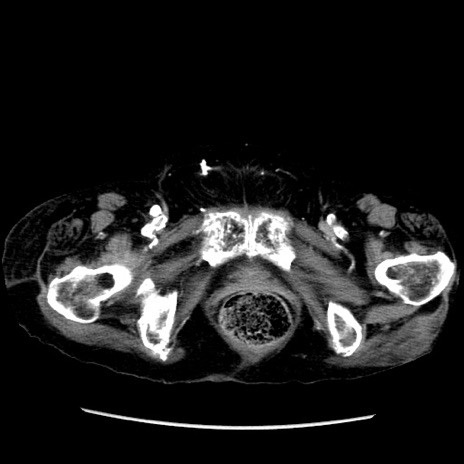

症例14(横断像)

【症例】 90歳代女性

【主訴】 腹痛・嘔吐

【現病歴】今朝から左側腹部痛を認めた。 経過観察していたが、嘔吐を認めたため来院。

【既往歴】 子宮癌術後

【身体所見】 意識清明、BP 127/54mmHg、P 98bpm Sp02 95%(RA)、BT 35.8°C、腹部平坦・軟腸ぜん動音聴取良好、右下腹部圧痛(+) 反跳痛なし

【データ】WBC 9800、CRP 0.46